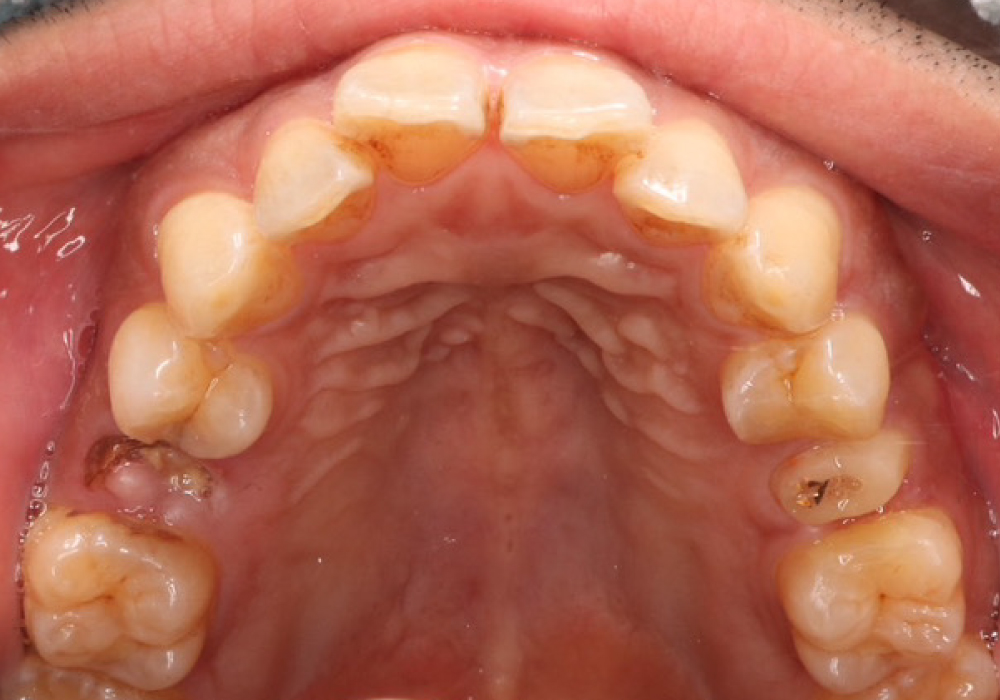

今日は、インプラントの症例をご紹介します。今回はだめな歯のところにインプラントをいれたいという40代男性の症例をご紹介します。気になる歯がどんどん悪化してきた、固いものが最近食べづらいという方、どうぞ参考にご覧ください。

40代男性

ご希望だめな歯のところにインプラントをいれたい。

抜歯